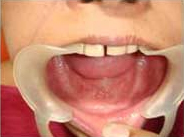

Use of Bone Graft & GTR membrane for an Implant

Before Placement of Prosthesis

After Placement of Prosthesis